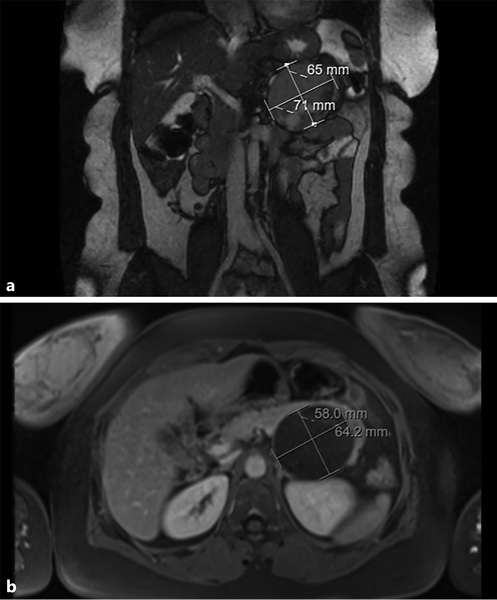

Similarly, magnetic resonance imaging (MRI) can be a valuable exam, and can even be considered superior to CECT since, apart from the fact that it lacks radiation and is safer in those who suffer from contrast allergy or renal insufficiency, it better characterizes the cystic component of the lesion. MRI shows an encapsulated lesion with solid and cystic components plus hemorrhage without internal septation (shown in Fig. 3). In addition, the signal intensity on T1- and T2-weighted images is heterogeneous, owing to the presence of hemorrhagic degeneration, which is hyperintense on T1-weighted images and has heterogenous signal intensity on T2 weighted images.

Fig. 3 T2-weighted (a) and T1-weighted (b) magnetic resonance images showing an encapsulated lesion in the body/tail of the pancreas, heterogeneously slightly hyperintense on the T2-weighted image and with low signal intensity on the T1-weighted image. Areas of hemorrhagic degeneration (low signal on the T2- and strong signal on the T1-weighted image) can also be seen.